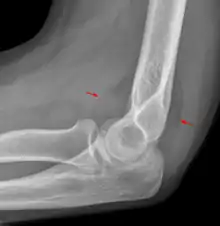

Fat pad sign

The fat pad sign, also known as the sail sign, is a potential finding on elbow radiography which suggests a fracture of one or more bones at the elbow. It is may indicate an occult fracture that is not directly visible. Its name derives from the fact that it has the shape of a spinnaker (sail).[1] It is caused by displacement of the fat pad around the elbow joint. Both anterior and posterior fat pad signs exist, and both can be found on the same X-ray.

In children, a posterior fat pad sign suggests a condylar fracture of the humerus. In adults it suggests a radial head fracture.

The fat pad sign is invaluable in assessing for the presence of an intra-articular fracture of the elbow. An anterior fat pad is often normal. However a posterior fat pad seen on a lateral x-ray of the elbow is always abnormal. The patient will be unable to flex their elbow and requires orthopaedic input.[2]